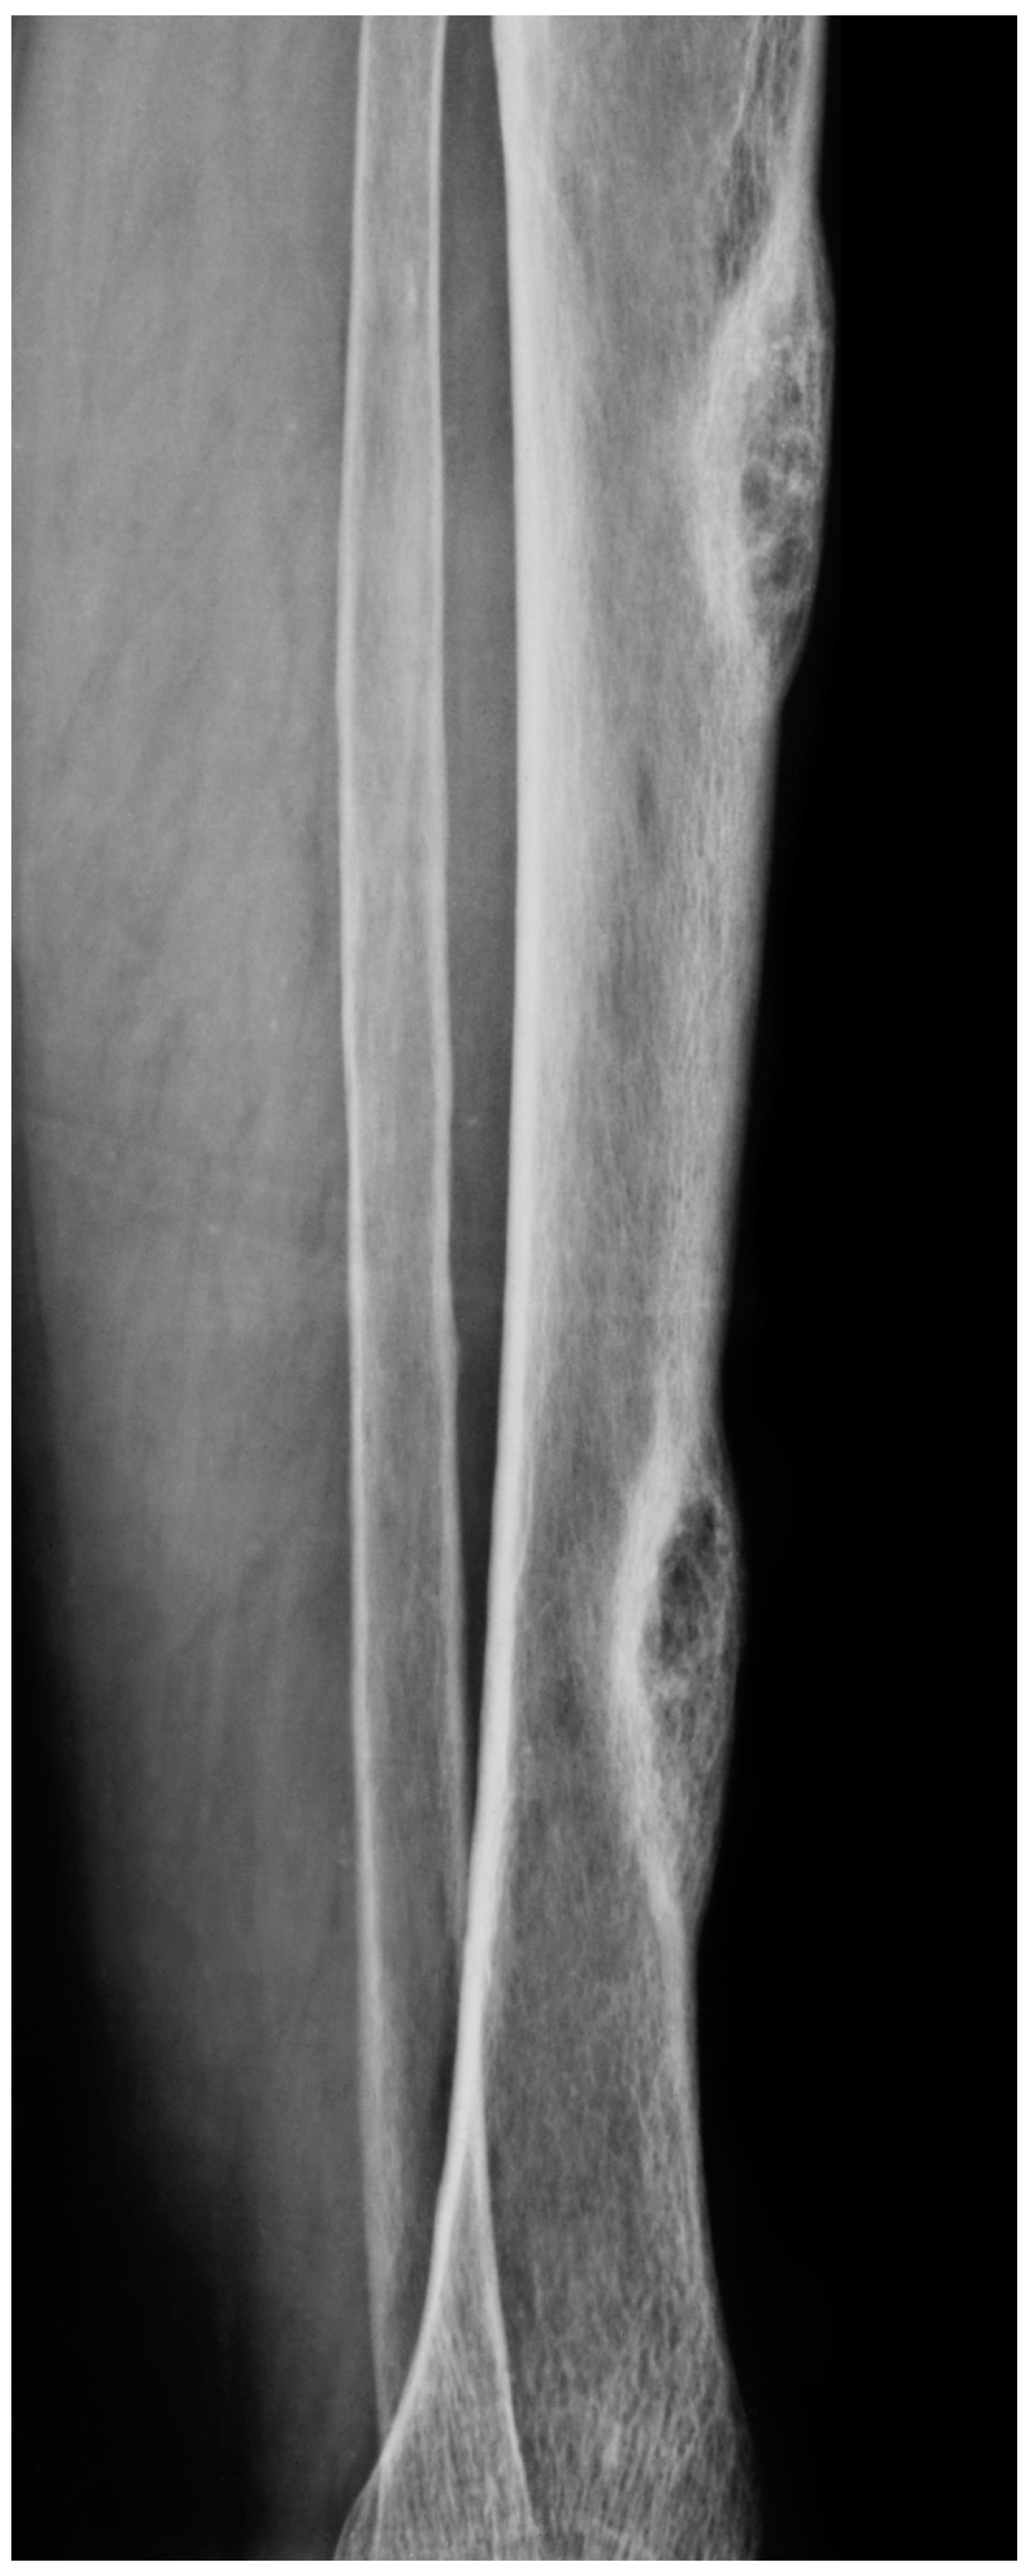

4.1. Radiological Imaging

4.2. Tissue Biopsy